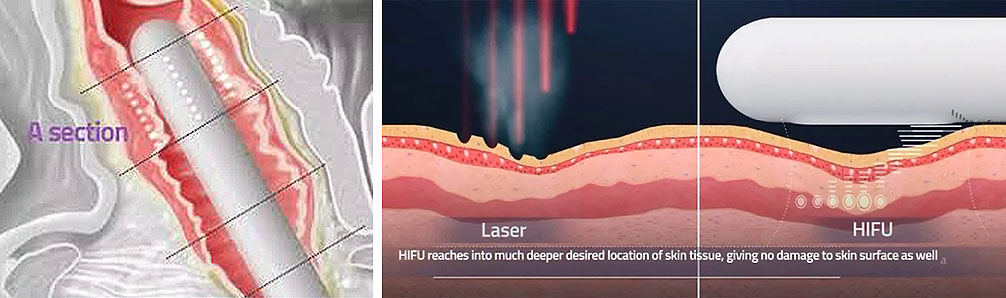

- There is no damage to the mucosa as is the case with laser treatments of the same area

Progression and effectiveness of treatment methods using HIFU technology are further substantiated by its application in treatments of severe diseases such as liver cancer, prostate cancer and uterine myomas. Advantages of this treatment method are preciseness and non-invasiveness.

The apparatus therapeutic effect is based on thermal effects enabling focused ultrasound waves to precisely target tissue and the depth NOT impairing any structures through which they travel. Transformation of HIFU waves energies into thermal energies achieves therapeutic effects which are exclusively NON-ABLATIVE and BIOSTIMULATIVE enabling the treatment to stimulateneosynthesis of collagen and its regeneration and reorganisation. It also encourages neovascularization of the treated area.

In recent years HIFU technology has been successfully applied in treatments of vaginal relaxation (VRS) and stress incontinence (SUI). Precise application of HIFU waves to vaginal walls at a depth of 3 to 4.5mm warms submucosa and mucous membrane to 65⁰C. This method practically instigates connective tissue of mucous membrane to regenerate. The treatment results in higher numbers of stronger, remodeled and narrowed collagen fibers which permeate and provide strength of vaginal walls. In addition, biostimulative effects of HIFU wave initiated regenerative processes have positive impacts on the elastic fibers of mucosa and pelvic muscles. Final results of the treatment are reflected by a narrowed vaginal canal with stronger, more resistant and healthier walls. All these effects are beneficial in the treatment of SUI hence why HIFU is also applied in treatments of first and second degree SUI whilst third degree SUI requires surgery. HIFU application in treatment of first and second degree SUI can significantly delay the development of third degree SUI and therefore delay or completely eliminate the need for surgical treatment.